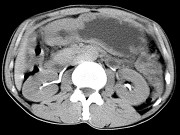

- 单项选择题男,56岁, 无规律上腹痛,左锁骨上淋巴结肿大, 消瘦、乏力,影像检查如图, 最可能诊断为 ( )

A、胃及腹腔淋巴瘤

B、胃癌并盆腔种植

C、胃溃疡穿孔

D、肠系膜淋巴管瘤

E、腹膜结核